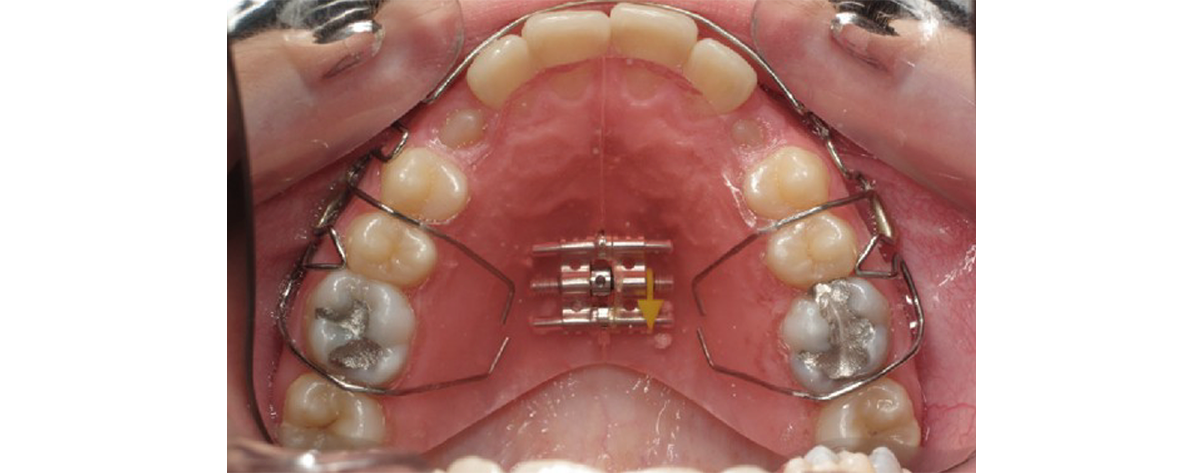

La plaque à vérin est un appareil permettant l’expansion du palais. Des petits tours au niveau du vérin sont à faire 1 à 2 fois par semaine par le patient. L’orthodontiste peut également activer le bandeau afin de redresser et resserrer les incisives. Cette plaque permet de corriger les articulés inversés, les incisives trop en avant ou en arrière.

Image de la dentition de la mâchoire supérieure avec la mise en place de la plaque à vérins à l’intérieur de la bouche.